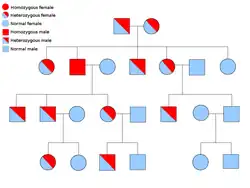

Two copies of every gene are present in all cells of the body and each one is called an allele. Most cancer syndromes are transmitted in a mendelian autosomal dominant manner. In these cases, only one faulty allele has to be present for an individual to have a predisposition to cancer. Individuals with one normal allele and one faulty allele are known as heterozygous. A heterozygous individual and a person with two normal alleles (homozygous) will have a 50% chance of producing an affected child.[9] The mutation in the inherited gene is known as a germline mutation and a further mutation in the normal allele results in the development of cancer. This is known as Knudson's two-hit hypothesis, where the first hit of the gene is the inherited mutation and the second hit occurs later in life.[2] As only one allele needs to be mutated (as compared to both in so-called "sporadic cancers"), the individual has a higher chance of developing the cancer than the general population.[10]

Less often, syndromes may be transmitted as an autosomal recessive trait. Both alleles of a gene must be mutated in autosomal recessive disorders for an individual to have a predisposition to cancer. A person with two recessive alleles is known as homozygous recessive. Both parents must have at least one faulty allele in order for a child to be homozygous recessive. If both parents have one mutant allele and one normal allele (heterozygous) then they have a 25% chance of producing a homozygous recessive child (has predisposition), 50% chance of producing a heterozygous child (carrier of the faulty gene) and 25% chance of produced a child with two normal alleles.[9]